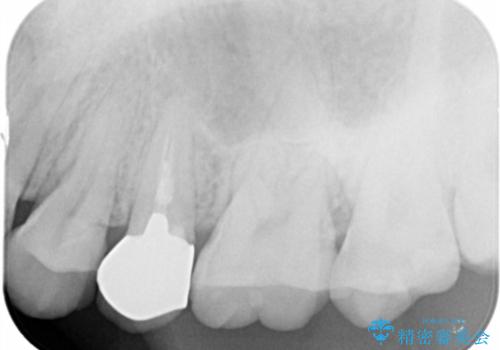

- 歯ぐきの腫れや、歯の内部が黒く見えることからの虫歯の治療を求めて来院されました。

虫歯が大きかったことから、神経の温存はできたものの歯ぐきよりも深い虫歯の問題を解決するため、部分矯正治療を併用したセラミック治療を行うこととしました。

当初、歯ぐきよりも深い虫歯の存在や、歯のポジションに問題がありましたがマルチブラケットを用いた部分矯正で行うことで歯の挺出同時に適切な位置へと歯を移動させ、歯周環境を整えたセラミック治療を行うことができました。